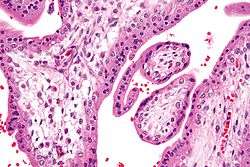

![]() Micrograph showing chorionic villi. Very high magnification. H&E stain. | |

Chorionic villi are villi that sprout from the chorion to provide maximum contact area with maternal blood.

They are an essential element in pregnancy from a histomorphologic perspective, and are, by definition, a product of conception. Branches of the umbilical arteries carry embryonic blood to the villi. After circulating through the capillaries of the villi, blood returns to the embryo through the umbilical vein. Thus, villi are part of the border between maternal and fetal blood during pregnancy.

Histology

The bulk of the villi consist of connective tissues that contain blood vessels. Most of the cells in the connective tissue core of the villi are fibroblasts. Macrophages known as Hofbauer cells are also present.